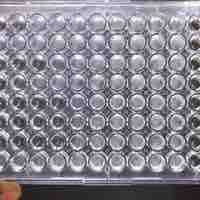

Minimum Inhibitory Concentration is the lowest drug concentration that prevents visible microorganism growth after overnight incubation.

Kirby-Bauer testing measures sensitivity of bacteria to antibiotics by culturing bacteria on solid growth media surrounding sources of drug.